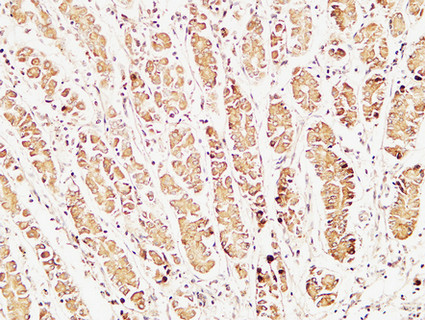

Immunohistochemistry analysis of paraffin-embedded Human stomach using Caspase 1 antibody.High-pressure and temperature Tris-EDTA pH 8.0 was used for antigen retrieval.